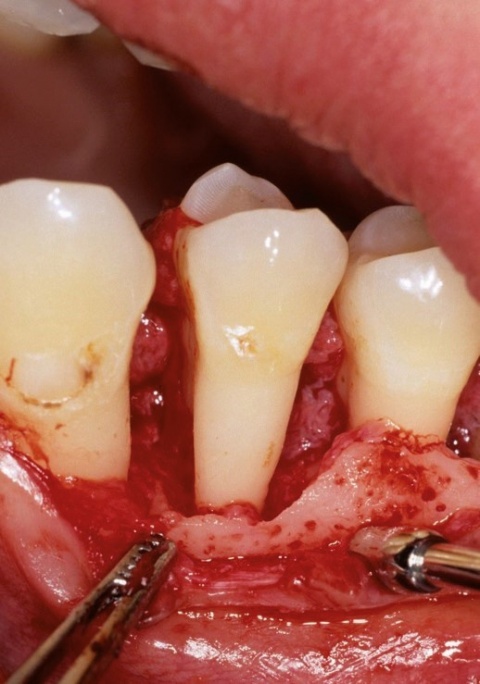

Fallbeispiel: Seminomatöser Hodentumor mit kontralateraler testikulärer intraepithelialer Neoplasie als Zufallsbefund In unserer urologischen Ambulanz (Bundeswehrkrankenhaus Ulm) stellte sich ein 28-jähriger Patient zur Abklärung einer Mikrohämaturie…